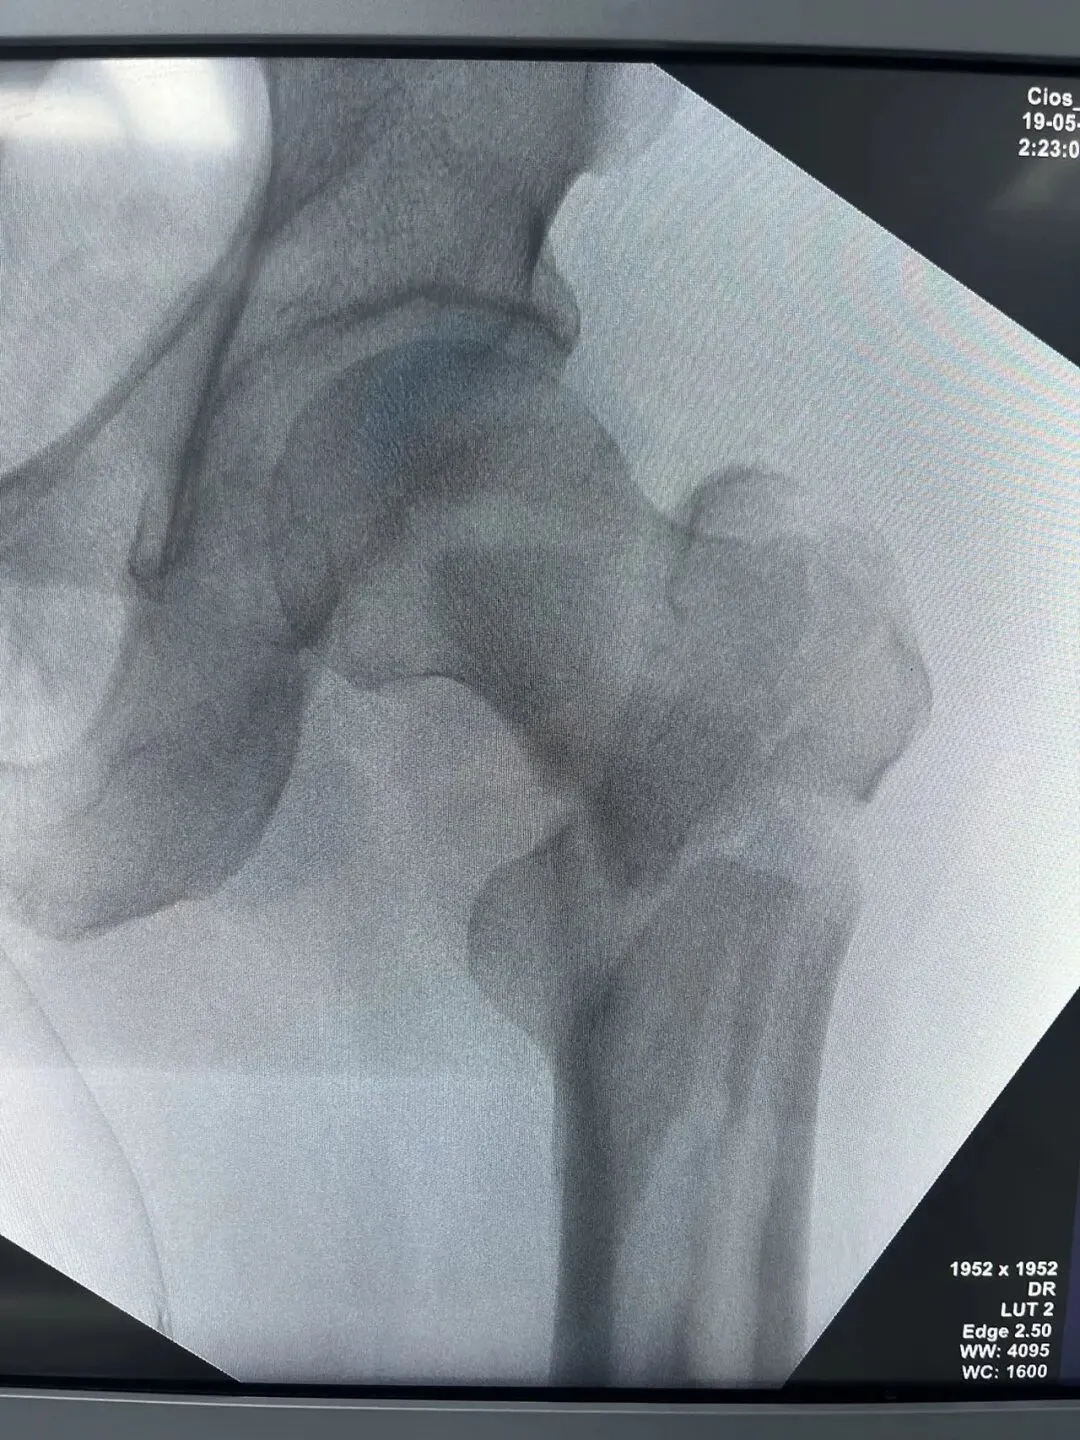

中老年男性,高处坠落伤,如此长节段股骨近端骨折比较少见。手术治疗是必须的,患者等待期间血栓风险极高。而且患者卧床骨牵引期间护理极其不方便,给家人造成很大困惑为早点解决患者病痛,入院后积极抗凝预防血栓,伤后第3天手术治疗。我们选择PFNA闭合复位内固定。手术还算顺利。

手术在牵引床上操作,近端开口器开口后用金手指找远折端,找到后顺势插入导针,剩下的就是套路了。如此长节段的股骨近端骨折,一定要做到闭合复位,保证骨折周围软组织铰链夹板完整,不破坏局部血运,才能保证骨折的顺利愈合。